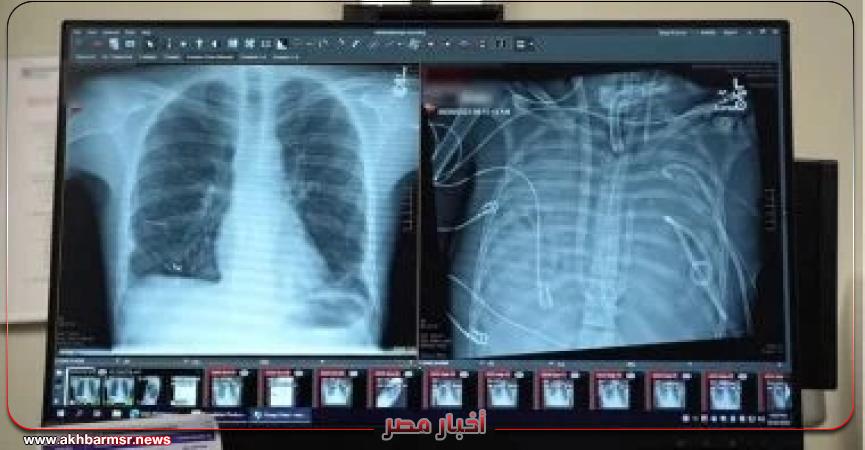

تمكن جراحون في مستشفى نورث وسترن ميديسن في شيكاغو، من إبقاء مريض في حالة حرجة على قيد الحياة لمدة 48 ساعة بعد إزالة كلتا رئتيه.

ووفقا لـ"Fox news"، فإن المريض، والذى يبلغ من العمر 33 عامًا ولم يتم الكشف عن اسمه، تم نقله جوًا في الأصل إلى مستشفى نورث وسترن التذكاري بسبب فشل رئوي مرتبط بعدوى الإنفلونزا في ربيع عام 2023، وعندما تفاقمت حالته إلى التهاب رئوي حاد وتسمم الدم، توقف قلبه وقام الفريق بإجراء الإنعاش القلبي الرئوي.

قام الفريق الطبي بتصميم "نظام الرئة الاصطناعية الكاملة (TAL) "، الذي تولى عملية تبادل الغازات (الأكسجة وإزالة ثاني أكسيد الكربون)، وحافظ على تدفق الدم إلى القلب على أمل أن يتمكن من إبقاء المريض على قيد الحياة بعد إزالة كلتا رئتيه المريضتين.

وأوضح بهارات قائلا :"يكمن الابتكار الرئيسي هنا في أننا حافظنا على وظائف القلب الطبيعية، من خلال استخدام تصميم "متكيف مع التدفق، مما سمح لقلب المريض بتنظيم تدفق الدم، بدلاً من إجباره بجهاز"، مضيفا أنه بعد يوم واحد فقط من استئصال الرئتين، بدأ جسد المريض يتحسن لأن العدوى قد زالت.

بعد مرور 48 ساعة، استقرت حالة المريض بما يكفي لإجراء عملية زرع رئة مزدوجة . وبعد عامين، عاد إلى حياته الطبيعية، موضحا إن حالة المريض جيدة بشكل ملحوظ. لديه وظائف رئوية ممتازة ، ووظائف قلبه سليمة، وهو مستقل تماماً في أداء وظائفه اليومية.